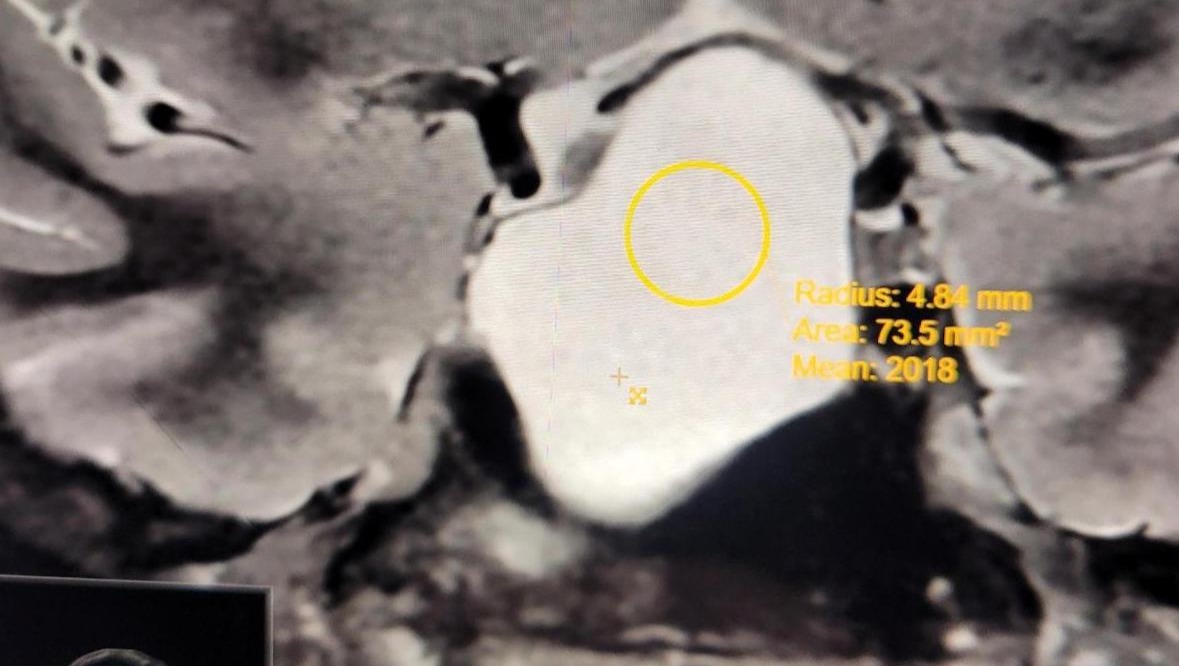

As of recent, Sara has been told she has to have surgery to remove a cyst that is pushing against her pituitary gland. The mass is the size of a golf ball and luckily benign, but still scary for her and her family. As of right now, this surgery will likely put her out of classes and work for at least 4 - 12 weeks.